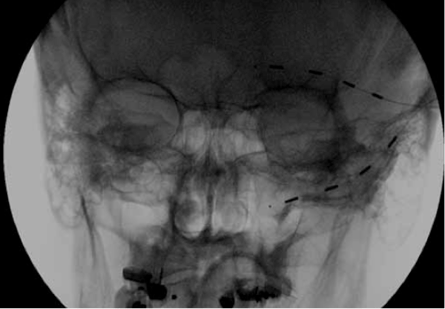

La référence Ellis JA, Mejia Munne JC, Winfree CJ. Trigeminal branch stimulation for the treatment of intractable craniofacial pain. Journal of neurosurgery. 2015:1-6 L'article La stimulation de la branche du trijumeau a été utilisée dans le traitement de douleur crânio-faciales mais les risques et les avantages de ce type d’approche n’ont pas été clairement définis dans les grandes études. Les auteurs rapportent leur expérience dans le traitement de la douleur crânio-faciales...